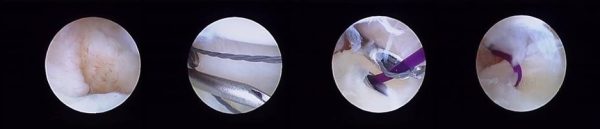

Αρχικά γίνεται μια διαγνωστική επισκόπηση της άρθρωσης, δηλαδή ελέγχεται όλη η πηχεοκαρπική, αλλά και η μεσοκάρπιος άρθρωση για τυχόν τραυματισμούς, εκφύλιση ή άλλου είδους βλάβη. Ακολουθεί διόρθωση των παθολογικών ευρημάτων.

Πολλές φορές η κάμερα υψηλής ευκρίνειας και μεγέθυνσης μάς αποκαλύπτει παθολογία που ειδάλλως δεν θα μπορούσαμε να δούμε.